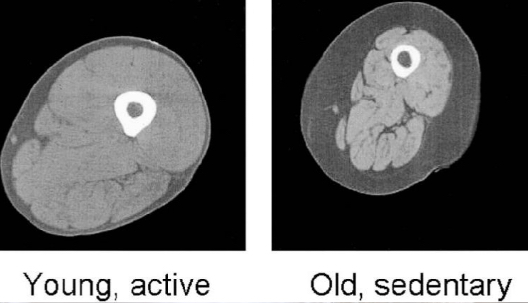

What is sarcopenia?

Weight/muscle loss due to old age.

Reduction in muscle fibres.

Affects ‘normal’ activity